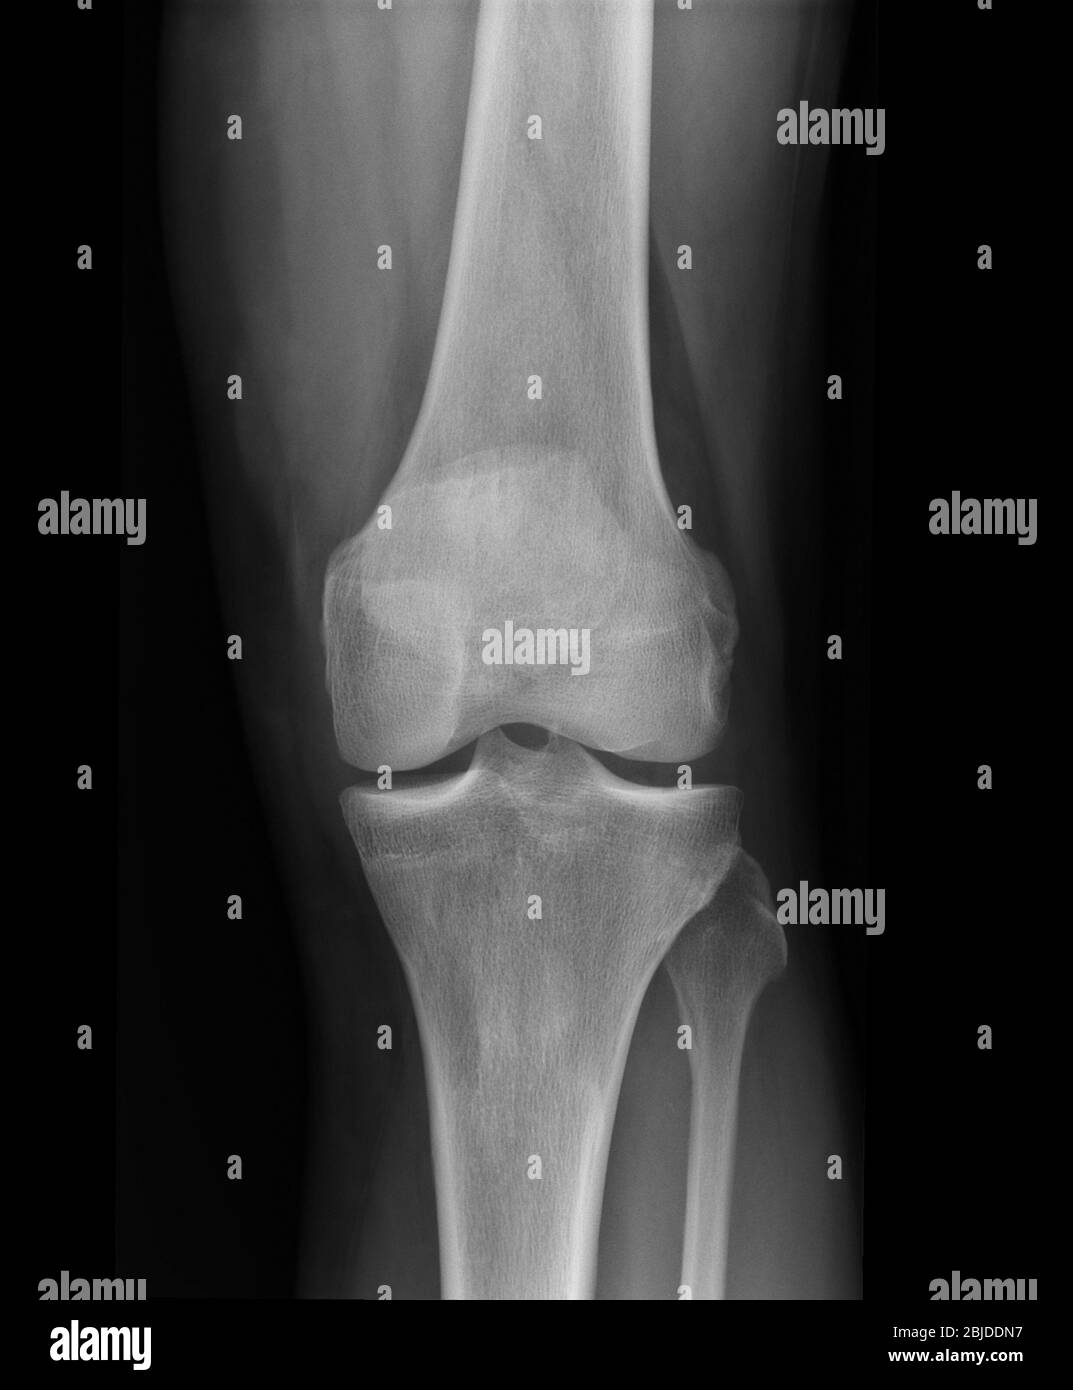

From www.alamyimages.fr

Fracture de la rotule Banque d'images noir et blanc Alamy Fracture De La Rotule Du Genou     — la fracture du genou concerne le plateau tibial (extrémité supérieure du tibia), le fémur distal (extrémité inférieure. Le trait de fracture est le plus fréquemment transverse, en plein corps de la rotule, traversant ainsi la surface cartilagineuse, il s’agit donc d’une articulaire pouvant causer ou favoriser l.    — chirurgie ?    — vous avez une fracture de. Fracture De La Rotule Du Genou.